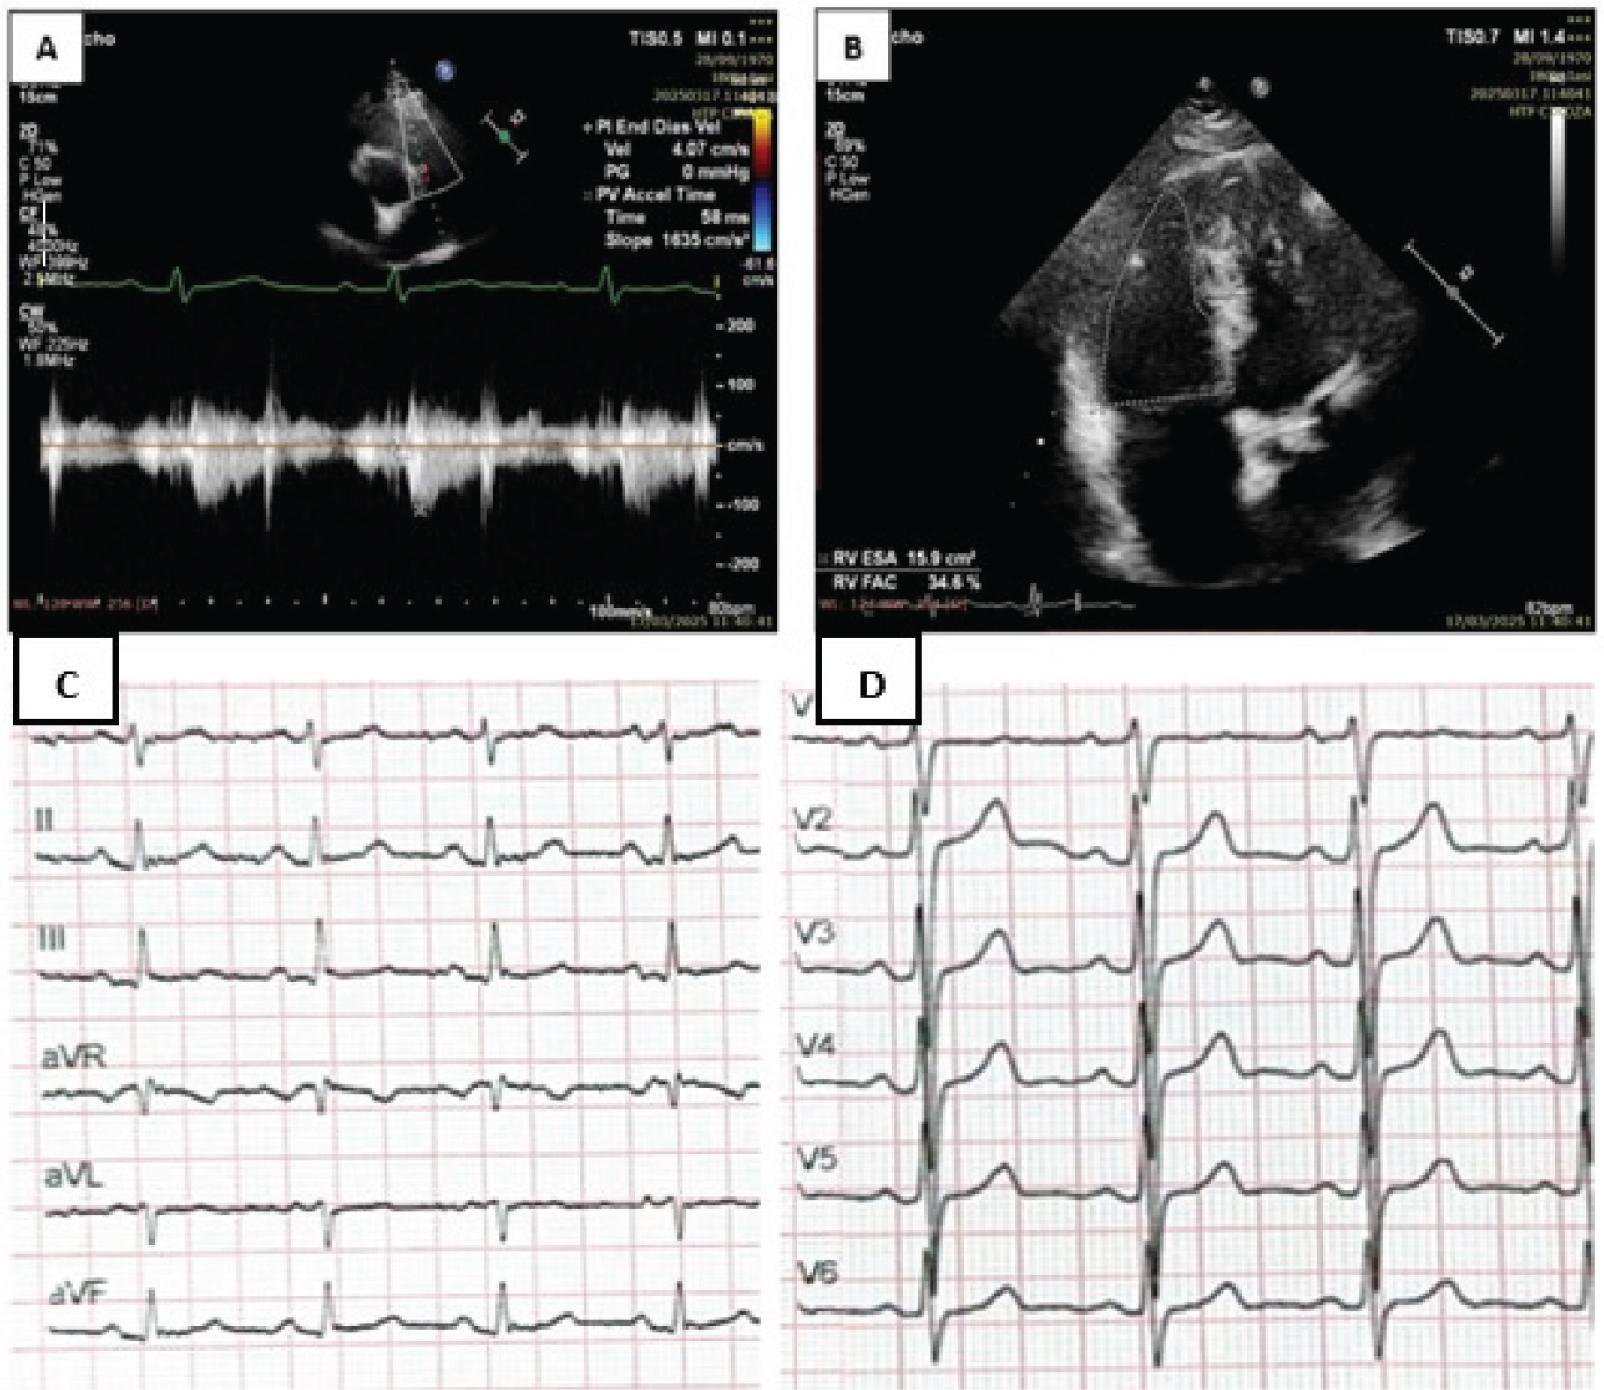

Transthoracic echocardiography (TTE) revealed a mildly dilated left ventricle (end-diastolic diameter 47 mm) without hypertrophy (interventricular septum 12 mm, posterior wall 11 mm) and a preserved systolic function, as reflected by a left ventricular ejection fraction of 65%. There were no findings suggestive of left heart disease. The right heart evaluation showed a right ventricular (RV) diameter of 39 mm and a right atrial (RA) volume of 52 mL. Estimated systolic pulmonary artery pressure (sPAP) was 58 mmHg, based on a right atrium–right ventricle (RA–RV) pressure gradient of 55 mmHg. Tricuspid annular plane systolic excursion (TAPSE) measured 21 mm, and pulmonary acceleration time (PAT) was 56 ms, consistent with elevated pulmonary pressure (Figures 2A and 2B). The TAPSE/sPAP ratio was calculated at 0.36 mm/mmHg, a value exceeding the 0.30 mm/mmHg prognostic threshold associated with better transplant-free survival in PoPH, as reported in recent studies (15). N-terminal pro-B-type natriuretic peptide (NT-proBNP) was 52.5 pg/mL, consistent with a low-risk PAH profile. These results, together with an Electrocardiography (ECG) showed sinus rhythm, rightward QRS axis (lead I predominantly negative, lead aVF predominantly positive, QRS axis >+90°), with R/S = 1 in V6, suggestive of right ventricular (RV) hypertrophy, and no ischaemic changes. Coronary angiography revealed no significant lesions. support a non-ischaemic and non-inflammatory aetiology for the patient’s elevated pulmonary pressures.

(A) TTE in the parasternal short-axis view revealed a PAT of 58 ms. A PAT <100 ms is suggestive of PH, while values <70 ms are typically associated with severe forms. (B) Echocardiographic assessment of right ventricular function showed an RVFAC of 34.6%, below the normal range of 35%–60%, consistent with global right ventricular systolic dysfunction. (C) ECG shows rightward axis: lead I predominantly negative QRS complex, lead aVF predominantly positive QRS complex, QRS axis >+90°; (D) ECG shows R/S = 1 in V6, which means clockwise rotation associated with right ventricular hypertrophy. PAT, pulmonary acceleration time; PH, pulmonary hypertension; RVFAC, right ventricular fractional area change; TTE, transthoracic echocardiography.